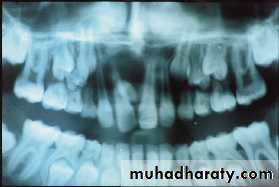

Ankylosed tooth: The tooth is in state of static retention, whereas in the adjacent areas eruption and alveolar growth continue.

Ankylosis of anterior teeth does not occur unless there has been trauma.

Diagnosis of ankylosed tooth:

1. Eruption has not occurred.

2. Alveolar process has not developed in normal occlusion.

3. The opposing tooth is out of occlusion.

4. Even with extensive root resorption, the tooth is not mobile.

5. Diagnosis by tapping with a blunt instrument.

6. Radiographically: A break in the continuity of the periodontal membrane.

Treatment of ankylosed tooth:

Early diagnosis is important.Treatment may involve surgical removal,

loss of arch length is evident, the dentist may choose to keep the tooth under observation.

The tooth that is definitely ankylosed may undergoes root resorption and be normally exfoliated.